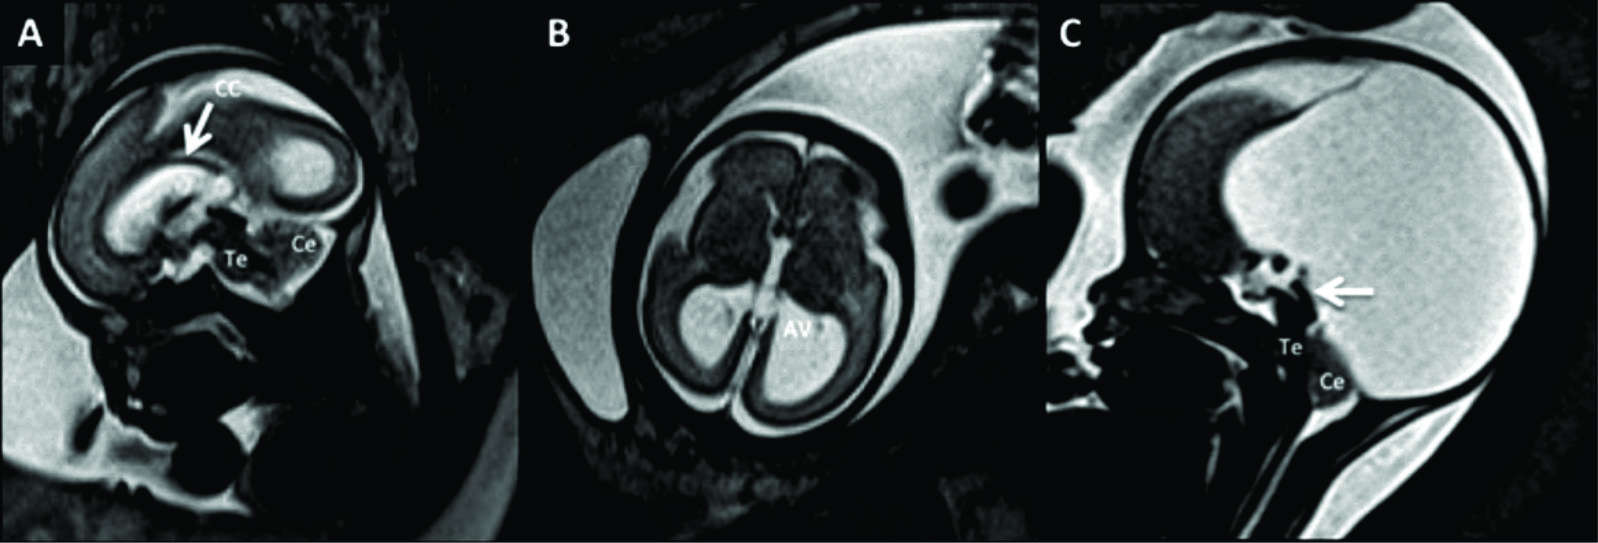

Figura 6

RM Fetal Agenesia del Cuerpo Calloso.

Estudio realizado a las 27 semanas de edad gestacional con diagnóstico de agenesia del CC. En imagen sagital (A) no se observa el CC ni la cisura pericallosa. Los gyrus de la cara mesial toman un aspecto radiado como suele observarse en esta entidad. Los ventrículos laterales (è) toman un aspecto colpocefálico de dirección ántero posterior como se ve en el corte axial (B).

Las estructuras de la fosa posterior son normales. Te: Tronco encefálico Ce: Cerebelo

Figura 7

RM Fetal Holoprosencefalia.

RMf a las 28 semanas referido por estudio ecográfico para confirmación de holoprosencefalia. En el plano coronal (A) se identifica la cavidad ventricular única con manto cerebral periférico adelgazado y la característica masa intermedia (MI) por la ausencia de división de ambos tálamos.

En el plano axial (B) los hallazgos son similares con ausencia de estructuras de la línea media como cisura inter-hemisférica u hoz cerebral. Te: Tronco encefálico

Figura 8

RM Fetal Esquizencefalia bilateral.

Estudio de RM realizado en la semana 29 con diagnóstico ecográfico de esquizencefalia bilateral. En el corte axial (A) y coronal (B) se reconocen las clásicas hendiduras que vinculan el sistema ventricular con el espacio sub-aracnoideo de la convexidad en ambos hemisferios.

Las estructuras de línea media son normales así como también el tronco encefálico (Te) y el resto de las estructuras intra-craneanas.